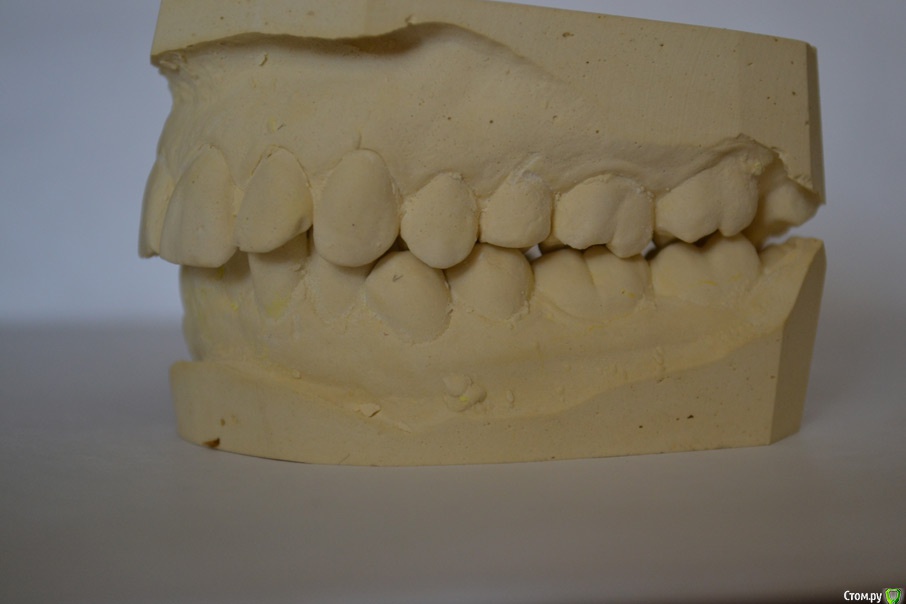

Здравстуйте! Мне 23 года.  У меня смещен центр верхней челюсти вправо и нижней влево. Больше беспокоит меня верх. На верхней челюсти, справа, отсутствует второй премоляр. На нижней клык слева. Премоляр мне в детстве удалили, он рос сверху зуба. Про нижний клык не помню. Проходила лечение не пластинке, не помню, к сожалению, почему. Очень хочу исправить эту ситуацию с зубами, но боюсь решиться, хочется получить гарантию от доктора, что все будет хорошо. Была на 3-х консультациях. На двух сказали что центр сместить нельзя. На одной доктор сказала, что нужно удалить сверху премоляр слева и снизу клык справа. Меня  интересует можно ли это исправить и каким методом, обязательно ли с удалением. Буду очень благодарна за помощь!!

1. с какой целью Вы хотите лечиться? только из-за средней линии??? это не мотивация к долгому трудному и недешевому лечению.  Ситуация в полости рта , конечно,  далека от идеальных зубных взаимоотношений , но с этим можно жить!  если нет явных жалоб на функцию, то часто оставляют как есть, природа сама всё скомпенсировала.

2. если все-таки хотите лечиться, то всё реально, только нужно запастись терпением.  Удалить все восьмерки, выставить средние линии, и  поставить импланты в область недостающих зубов.  Это вариант - максимум.

3. если хотите вариант минимум и просто что-то удалить наверху ради средней линии - то я бы не рекомендовала бы вообще тогда что-либо делать! сейчас у Вас всё скомпенсировано, а после ТАКИХ удалений очень высокая вероятность что начнутся уже реальные проблемы! да и с эстетической точки результатом Вы вряд ли останетесь довольны.